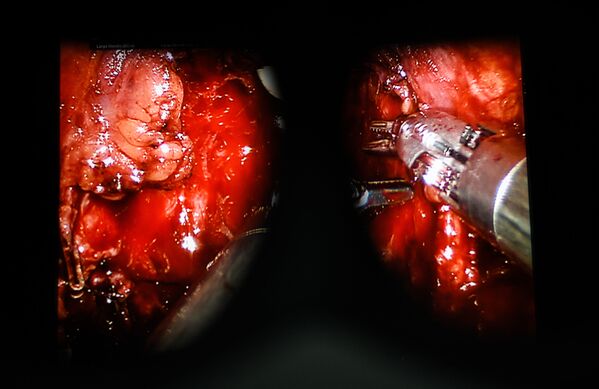

En estas imágenes puedes ver una operación realizada con la ayuda del robot cirujano Da Vinci en una de las clínicas de Moscú.

El robot tiene cuatro brazos. Tres de ellos tienen instrumentos quirúrgicos y el cuarto tiene una cámara 3D.

El cirujano controla las extremidades del robot con una palanca, manivelas y pedales. Observa lo que sucede a través de un monitor. La imagen es 10-15 veces más grande que la original y tridimensional. De hecho, se proporciona una visibilidad absoluta y capacidad de micromanipulación.